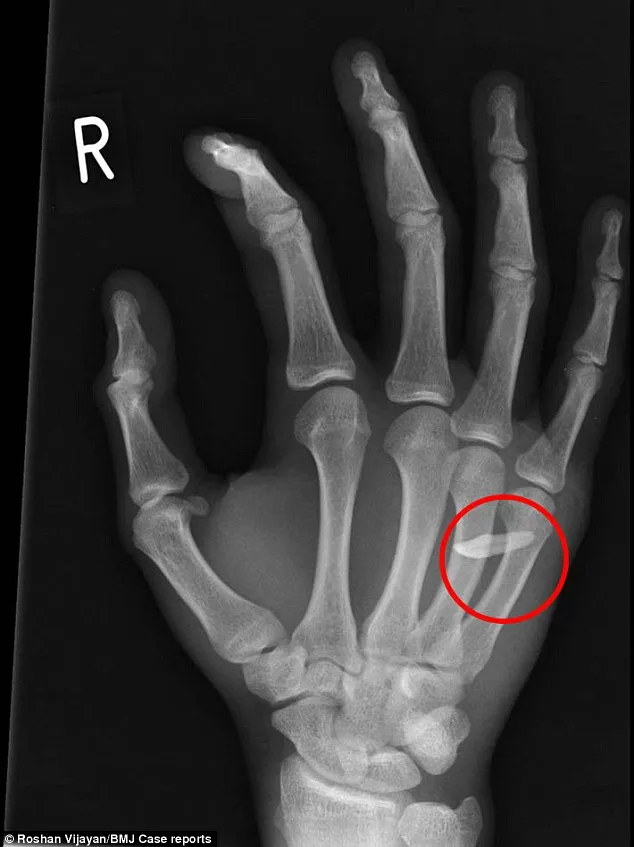

Ảnh X-quang cho thấy chiếc răng đã 'chui vào' bàn tay của bệnh nhân (Nguồn: Daily Mail)

Bác sĩ chẩn đoán anh bị nhiễm trùng do một vết cắn và yêu cầu chụp X-quang. Ngay sau đó, họ sửng sốt khi phát hiện ra cả một chiếc răng người găm vào bàn tay của người thanh niên.

Tế bào cơ xung quanh chiếc răng nằm giữa ngón áp út và ngón út đã chết. Vết thương sau phải để trong trạng thái mở trong một ngày và anh chàng phải giữ tay mình trong trạng thái lơ lửng suốt 1 đêm trong bệnh viện để bác sỹ quan sát. Ngày hôm sau, anh ta được phẫu thuật để khâu lại vết thương. Anh ta xuất viện hai ngày sau đó.